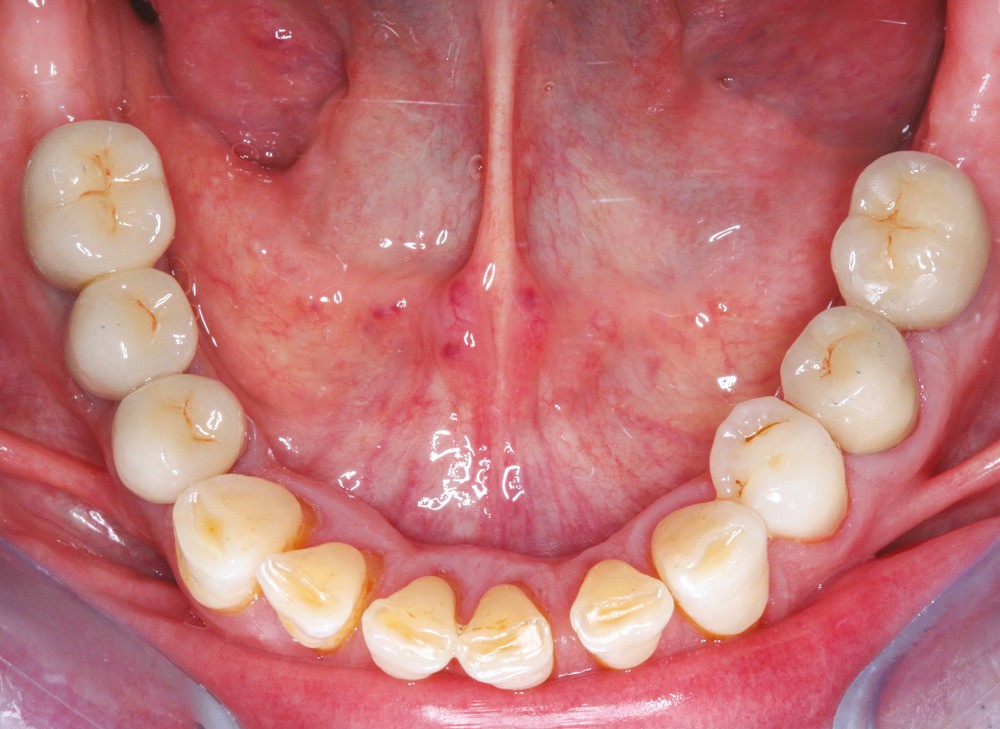

Le principe de protection mutuelle implique que les dents postérieures protègent les antérieures lors de la mastication. Des extractions non compensées de molaires, par exemple, entraîneront une hypersollicitation des antérieures et une usure importante du fait du principe de calage ainsi qu’un risque de perte de dimension verticale (fig. 10 à 13).

Des extractions multiples non compensées peuvent aussi occasionner une usure excessive des dents restantes, en raison de leur sollicitation occlusale trop importante.

L’abstention thérapeutique est une option envisageable lors d’extractions dentaires. Cependant, une surveillance est nécessaire et une analyse du cas clinique (âge du patient, position et nombre des dents absentes par exemple) est recommandée pour ne pas observer les conséquences évoquées ici. La réhabilitation de patient sur le modèle de l’arcade courte est une thérapeutique validée scientifiquement, et satisfaisante pour les patients (fig. 24 et 25).